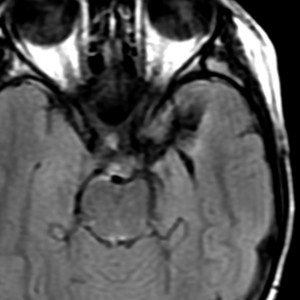

強直発作tonic seizureと夜間の嘔気発作で発症した女の子の乏突起星細胞腫です。海馬鉤と扁桃体を侵す内側側頭葉神経膠腫 mesial temporal gliomaと呼ばれる腫瘍です。特に小児に難治性てんかんを生じることで有名です。

T2強調画像とフレア画像でまだらな高信号を示しますが,境界は比較的明瞭です。限局性グリオーマ localized gliomaと呼ばれるタイプです。

CTでもMRIでも全く増強されません。

病理像です。左側の部分はperinuclear hallowが多い典型的な乏突起膠腫です。右側の部分ではびまん性星細胞腫の像ですが,その中に乏突起膠腫に特徴的なchicken wireと呼ばれる細い血管網も見られます。乏突起星細胞腫と呼ばれるのですが、腫瘍性格は乏突起膠腫と同じもので,星細胞系腫瘍には入りません。1p/19q欠失があるもののIDH変異がないのでoligoastrocytoma, NOSです。

術後のMRIです。腫瘍は全摘できていて再発はありません。手術でとても大切なことは,てんかん原性のある海馬鉤の腫瘍を摘出するだけではなくて,扁桃体切除 amygdalectomyも加えることです。それによって症候性てんかんをmedication freeにもっていける可能性があがります。扁桃体は片側(この場合は左)切除しても症状は出ません。